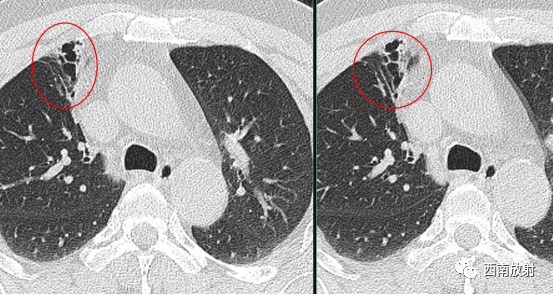

判断支气管扩张症的 MSCT表现,依据病变的程度、走行方向扫描层面有一定的关系。而印戒征和轨道征见于柱状支气管扩张,正常支气管管径稍小于伴行的肺动脉, 若支气管管径大于伴行的肺动脉直径,且此时的走行方向与扫描图像层面垂直,即构成特征性的印戒征。

▲图:支气管扩张,印戒征,支气管扩张旁边伴随肺动脉影。

当扩大的支气管走行与扫描图像层面平行时,表现为轨道征。扫描层面有时与支气管不垂直或平行时,可以通过图像重建弥补。

▲图:柱状支气管扩张,在扩张的支气管与扫描层面平行时,出现双轨征。